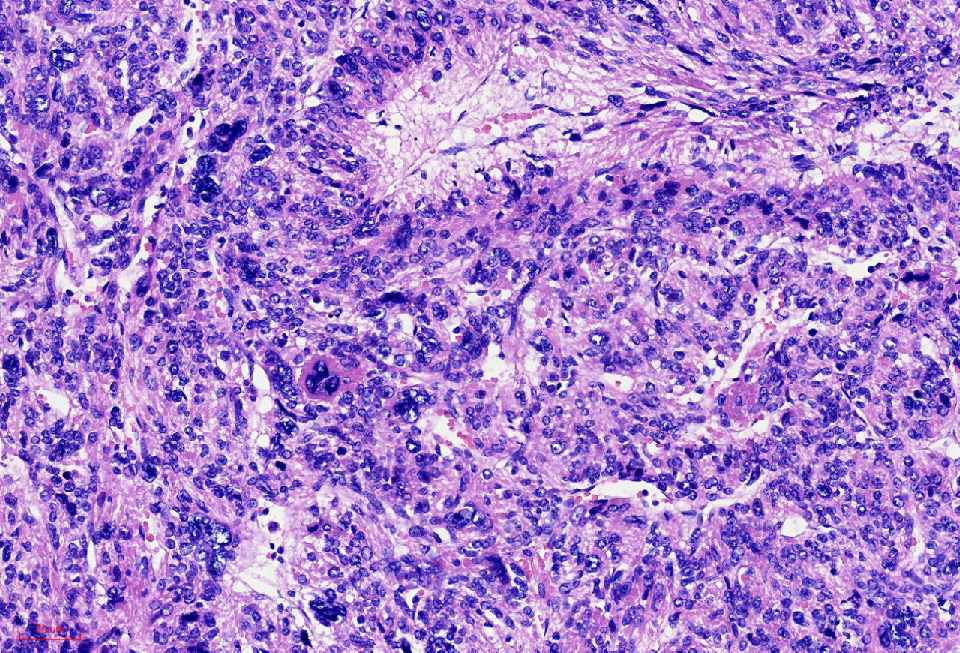

组织学改变

异型明显,可见核内包涵体,红核仁

细胞核奇异,嗜酸性胞质,有显著的嗜酸性核仁,核仁周围可见空晕,部分细胞呈横纹肌样

核分裂象少见

无凝固性坏死